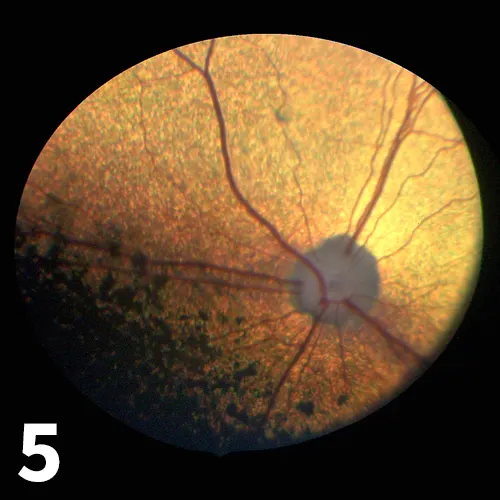

The 2 leading differential diagnoses for such a presentation are sudden acquired retinal degeneration (SARD) and optic neuritis affecting retrobulbar parts of the optic nerve (which is why the optic disc is normal-looking), up to and including the optic chiasm. The 2 may be differentiated by referring the patient for electroretinographic recording of retinal function, which will be normal in optic neuritis and absent in SARD (Figure 5). The recording has important prognostic implications; there is no proven treatment for SARD, but optic neuritis cases should be evaluated neurologically, as some cases, such as those caused by infectious diseases or granulomatous meningoencephalitis have systemic ramifications, and may be treated successfully.8,9

Figure 5

The normal-looking fundus of a 9-year-old Labrador retriever diagnosed with SARD.